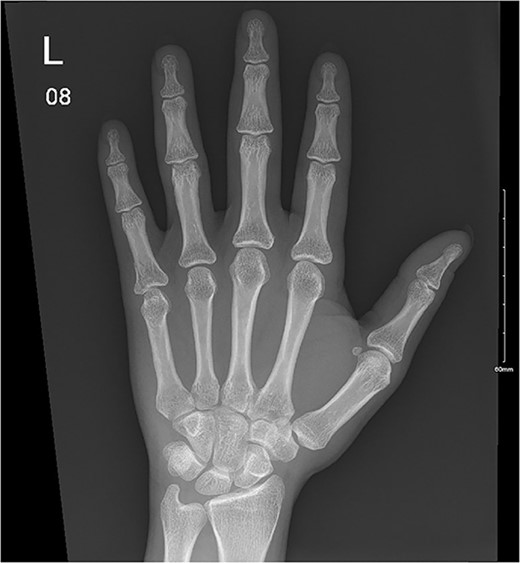

A 32-year-old male presented to the emergency department with a painful, discolored, and edematous left thumb following spontaneous deployment of his automobile’s airbag. On physical examination, the thumb’s range of motion (ROM) was reduced because of pain. Radiography showed a tuft fracture of the thumb’s distal phalanx (Fig. 1). The patient was managed conservatively with a Zimmer splint and followed-up 1 week later. Magnetic resonance imaging (MRI) was obtained to assess for the presence of ligamentous injury showed complete tearing and proximal retraction of the distal attachment of the ulnar collateral ligament in (Fig. 2), so the patient was given a thumb spica and was booked for surgery. In the operating room, the ulnar collateral ligament was identified and was indeed completely avulsed from its distal attachment site. The ligament was repaired using the Kessler tendon repair maneuver, ultimately ending with the thumb flexed 30° at the metacarpophalangeal (MCP) joint. This patient was followed-up for 103 days after his first presentation. On his final clinic visit, the thumb was stable, the wound was fully healed, and full ROM was regained.

Complete tear of ulnar collateral ligament with significant proximal retraction.